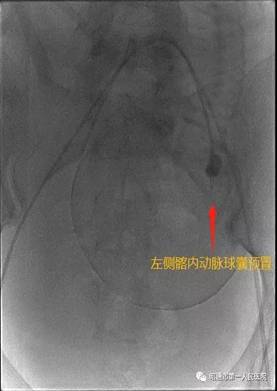

近日我院产科收治了一名由县级医院转入的孕妇。该孕妇年龄33岁,孕期多次B超提示:中央性前置胎盘伴植入可能。孕妇于2012年在其他医院行剖宫产术,2017年因瘢痕妊娠在云大医院行介入下手术。该孕妇入院后科室手术团队反复在科内B超下评估,结合她的病史及辅助资料考虑该患者胎盘植入的可能性很大,病情危急,决定术前邀请请普三科主任赵雄会诊。经会诊后拟术前行双侧髂内动脉球囊导管临时置入术。

术中见子宫下段血管丰富,怒张明显,胎盘广泛植入于子宫下段,伴穿透。如果按传统的胎盘打洞开窗取胎手术,孕妇可能瞬间大出血,危及生命。产科主任曹华及团队医师临时应变,经讨论决定借鉴省内外处理凶险性前置胎盘成功的经验,大胆探索子宫双切口术式,在接近宫底部取第一切口娩出胎儿后,由普三科手术团队行双侧髂内球囊临时阻断,子宫切口出血立即减少,剥离子宫切口周围胎盘组织,关闭第一切口。下推膀胱于子宫下段取第二切口,手剥胎盘,关闭第二切口。